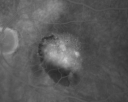

Retinal Vasculopathy associated with Facioscapulohumeral Muscular Dystrophy line os633 views59-year-old woman had a blood pressure spike to 170/90 and was on medications for that. She does have facioscapulohumeral muscular dystrophy, which runs in her family. She has a cousin with the same disorder.

VISUAL ACUITY: Her vision is 20/25 OU. IOP: OD 21, OS 18.

There is no posterior vitreous separation, telangiectatic vessels near the macula. There are patchy retinal hemorrhages. There is no edema or proliferation.